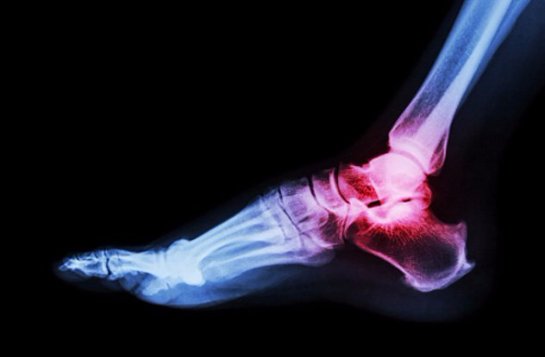

Боль. Бьетесь вы пальцем ноги об угол кровати, режетесь во время бритья или входите в закрытую дверь, все люди регулярно испытывают это чувство. Фармацевтические компании делают миллиарды, создавая обезболивающие, но секрет истинной нечувствительности к боли скрывается в мутантных генах, которые появляются относительно редко.

Ген SCN11A определяет количество натрия в клетках организма. Это может звучать не очень впечатляюще, пока вы не поймете, что нервные клетки используют натрий, посылая болевой сигнал. Если мутантный ген понижает уровень натрия, нервные клетки не имеют достаточного количества вещества, чтобы посылать такие сигналы, делая тела невосприимчивым к боли.

Что странно, эти люди чаще других ломают кости и вообще страдают от случайного членовредительства. В отсутствие боли, которая говорит им, что чего-то делать не стоит, они имеют тенденцию к травмированию себя, особенно в детством возрасте. Тем не менее их мутантные гены являются невероятно редкими и ценными, так что могут быть ключом к революционным новым обезболивающим.